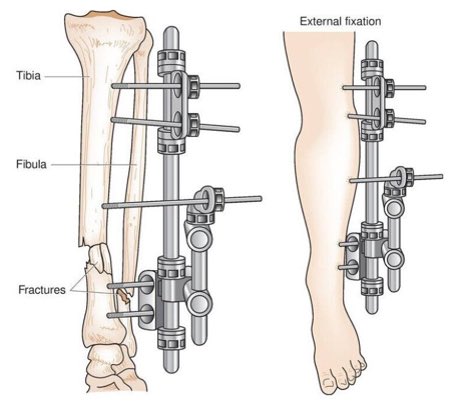

◻️ التشريح

تتكون الساق من عظمة الظنبوب (Tibia) في الجانب الأقرب للوسط، والشظية (Fibula) على الجانب الخارجي، ترتبط العظمتين بالغشاء بين العظمي (Interosseous membrane) في الساق مشكلًا نوع من المفاصل الليفية يدعى التلازم (Syndesmosis) ذات الحركة القليلة جدًا.

وتشارك عظمة الساق الظنبوب في مفصل الركبة من الأعلى ومفصل الكاحل من الأسفل، أما الشظية لا تشارك في مفصل الركبة.

- التثبيت الخارجي (External fixation): عبارة عن إطار خارج الساق يتم تثبيته في العظام بدبابيس، يوفر هذا الجهاز الثبات للعظام خلال فترة الالتئام و تتم إزالته عادة بعد التئام الكسر.